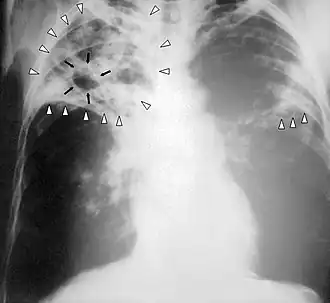

| Radiografia ao peito de uma pessoa com tuberculose avançada. As setas brancas assinalam a infeção em ambos os pulmões. As setas pretas assinalam a formação de uma cavidade. | |

Em tuberculose pulmonar ativa, infiltrações ou consolidações e/ou cavidades são frequentemente vistas na parte superior dos pulmões com ou sem linfadenopatia (doença nos nódulos linfáticos) mediastinal ou hilar. No entanto, lesões podem aparecer em qualquer lugar nos pulmões. Em pessoas com HIV e outras imunossupressões, qualquer anormalidade pode indicar a tuberculose, ou o raio-x dos pulmões pode até mesmo parecer inteiramente normal.